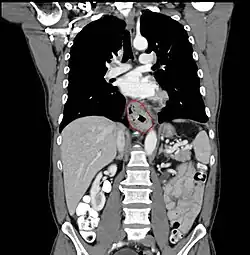

- Lower thoracic esophagus and EG junction:

- Inferior pulmonary veins to the stomach; includes the intraabdominal portion of the esophagus

- By endoscopy, 30 to 40 cm

- For cancers arising near the EGJ, they are staged as esophageal/EGJ if the epicenter is in the lower thoracic esophagus, the EGJ, or within the proximal 5 cm of the stomach (cardia) and extend into the EGJ or esophagus

- Those with an epicenter in the stomach greater than 5 cm distal the EGJ, or those within 5 cm of the EGJ but that do not extend into the EGJ or esophagus, are staged as gastric

- GE junction: (Classification by Siewert: PMID 11525305, PMID 9823902), center within 5 cm proximal/distal to GEJ

- Type I (distal esophagus) - arises from area with specialized intestinal metaplasia of the esophagus. Commonly, center of the tumor located 1 - 5 cm above the gastroesophageal junction

- Type II (cardia, considered gastric) - arises from the cardiac epithelium or short segments with intestinal metaplasia at the GEJ. Commonly, center of the tumor located 1 cm above to 2 cm distal to GEJ

- Type III (sub-cardia, considered gastric) - arises from subcardial location and infiltrates GEJ from below. Commonly, center of tumor >2 cm distal to GEJ